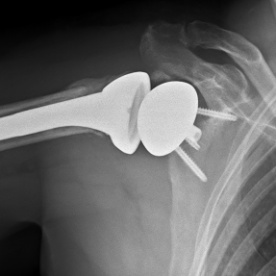

Röntgenbilder